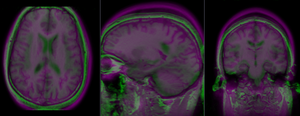

RegLib C10 registered2 Affine.gif after affine registration (click to enlarge)

RegLib C10 registered3 BSpline.gif after nonrigid BSpline (5x5x3) registration (click to enlarge)

RegLib C10 registered4 BSpline2.gif after nonrigid BSpline (7x7x5) registration (click to enlarge)